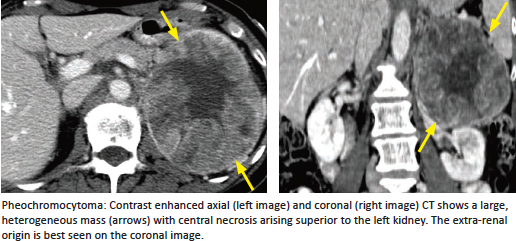

Pheochromocytoma

What is it?

Symptoms?

What is the name for an extra-adrenal pheo? Most common location? Rare location causing distinctive clinical presentation?

“Rule of 10s”

Syndromes it is associated with?